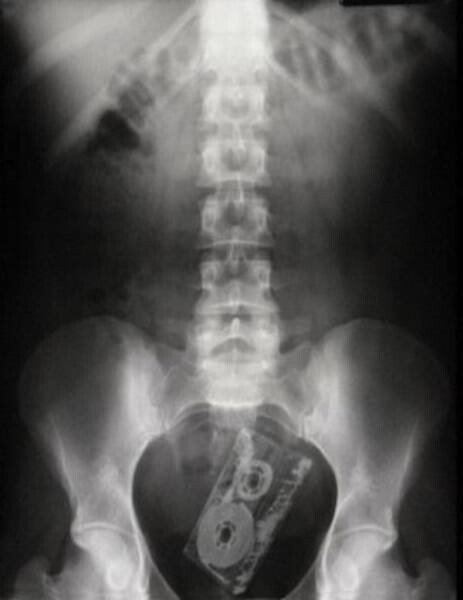

14. Несомненно зажигательный сборник